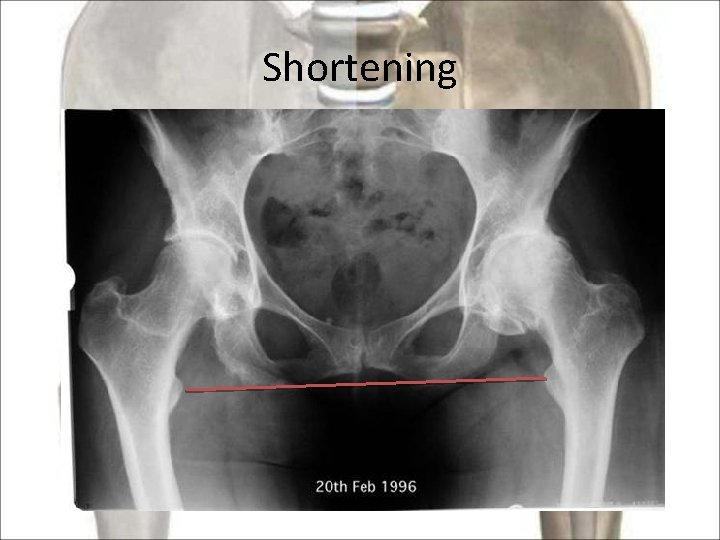

Shortening